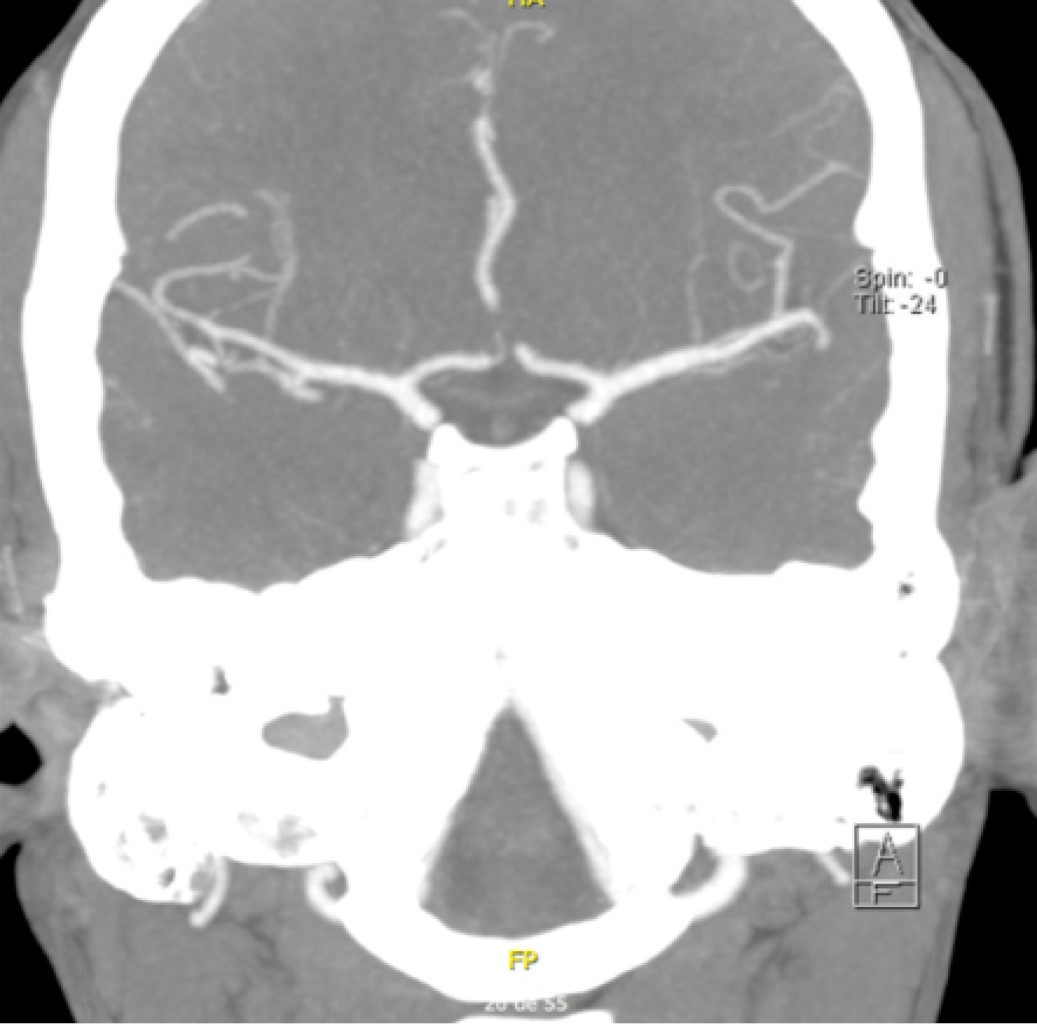

Presentamos el caso de una mujer de 34 años que ingresa por cuadro clínico de instauración súbita de 2 horas de evolución con afasia no fluida y hemiparesia derecha. Como antecedente médico tiene historia de macroadenoma hipofisiario con apoplejía pituitaria y escaso sangrado intratumoral 11 meses previos a su ingreso (Figura 1).

Figura 1